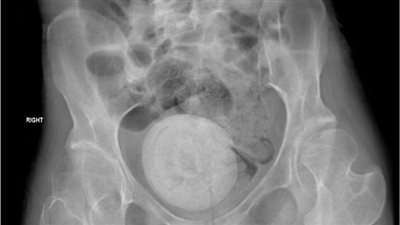

حالة طبية نادرة.. اكتشاف حصوة مهبلية بحجم برتقالة كبيرة في حوض امرأة